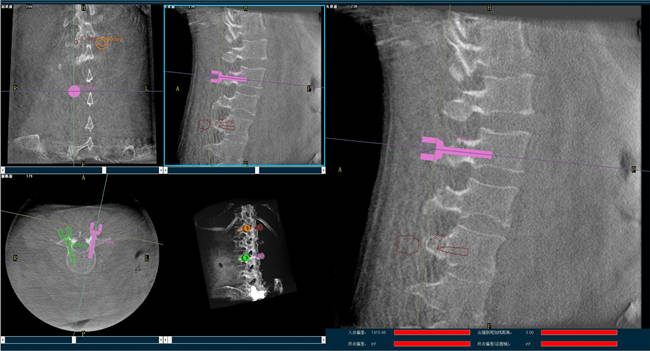

迄今,術(shù)前規(guī)劃已經(jīng)成為骨科手術(shù)的“前哨守衛(wèi)”,目前的脊柱外科手術(shù)機(jī)器人可以通過人工智能算法做到精準(zhǔn)的脊柱分節(jié)段識別并模擬重現(xiàn)患者的生理特征與骨骼排列,讓手術(shù)既準(zhǔn)確又安全;尤其在脊柱外科手術(shù)中可以發(fā)揮很大作用,避免產(chǎn)生對周圍神經(jīng)、椎管內(nèi)脊髓的損害,減少并發(fā)癥的出現(xiàn)。

以椎弓根螺釘置入手術(shù)為例,有時候?yàn)榱藴?zhǔn)確定位,甚至需要將椎弓根螺釘多次進(jìn)出、反復(fù)選擇,這樣無疑就增加了脊髓神經(jīng)損傷的風(fēng)險,降低了螺釘把持力。但脊柱外科手術(shù)機(jī)器人可以在術(shù)前規(guī)劃把手術(shù)入路、方向、釘子的深度都做好規(guī)劃,手術(shù)前就在電腦上規(guī)劃好進(jìn)釘?shù)奈恢?,在手術(shù)中利用機(jī)器人系統(tǒng)“(脊柱)分節(jié)段單椎體識別”、“釘棒一體化”、“術(shù)中全程可視”等特性,做到“一步到位”,因此,比起傳統(tǒng)手術(shù),機(jī)器人手術(shù)更加安全。同時,目前機(jī)器人技術(shù)的透視檢查時長、每顆螺釘置入時長和住院時長均比術(shù)中使用3D-CT導(dǎo)航更短,提升手術(shù)效率。